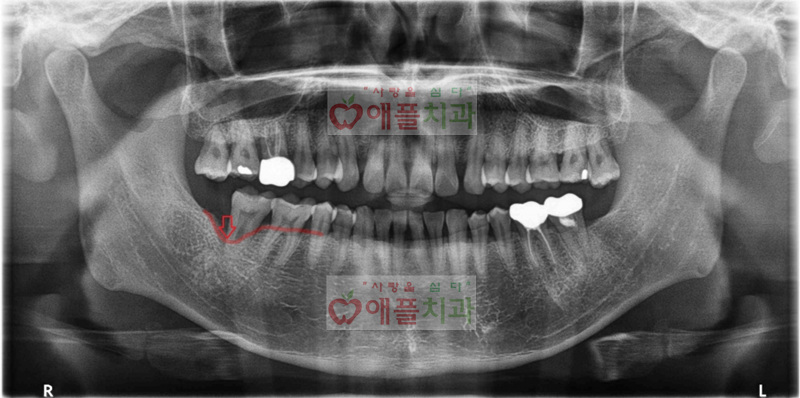

< 처음 내원시 엑스레이>

우측 아래 어금니가 아파서 내원하셨습니다.

발치가 불가피하다고 설명드리면서 발치후 3개월 뒤에 임플란트 수술을 진행하였습니다. 잇몸뼈가 많이 흡수되어있어 골이식과 동시에 임플란트 수술을 진행하였습니다.